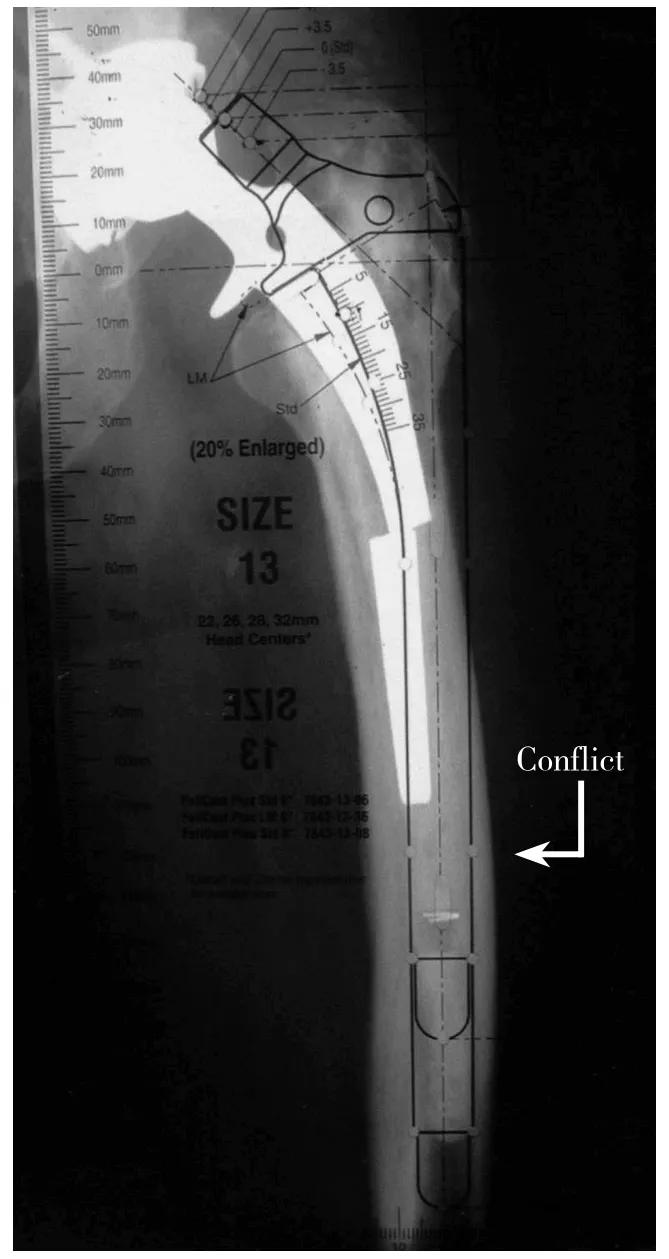

术前X线测量评估时一个重要而又易被忽略的部分是对股骨畸形的评估。松动的股骨假体常伴有股骨重塑(remodelling)致内翻和后倾畸形,而术前模板测量有助于辨识股骨重塑。图1-3-7所示:用模板测量时,植入假体柄的远端部分应放于股骨髓腔中央,柄的外侧边界与股骨外侧皮质之间的位置关系可以对比出来。如果假体接触或位于股骨外侧皮质之外,则提示发生了股骨内翻重塑,此时就应该决定在术中显露时做ETO,否则术中扩髓时将会有股骨穿孔的风险,若自髓腔植入假体尺寸不合适,还可能导致骨折。

术前模板测量有助于辨识股骨重塑